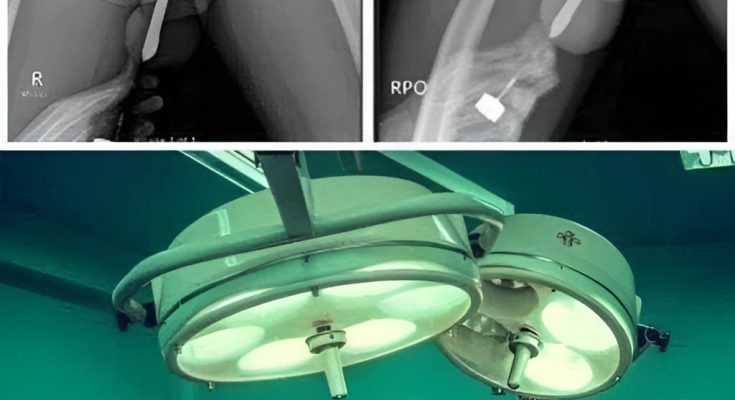

The X-ray That Explained Everything

Once she arrived at the emergency room, doctors began running tests. Because the cause of her pain was unclear, they ordered a scan to rule out internal bleeding or abdominal complications. What they found instead was the household tool lodged deeper inside her body than she realized — not due to intentional usage, but due to the angle, force, and the completely accidental way it had slipped.

The medical team immediately prepared for a controlled procedure to remove the object safely, as improper handling could worsen the injury. Fortunately, they were able to retrieve it without major surgical intervention, and there were no long-term complications.